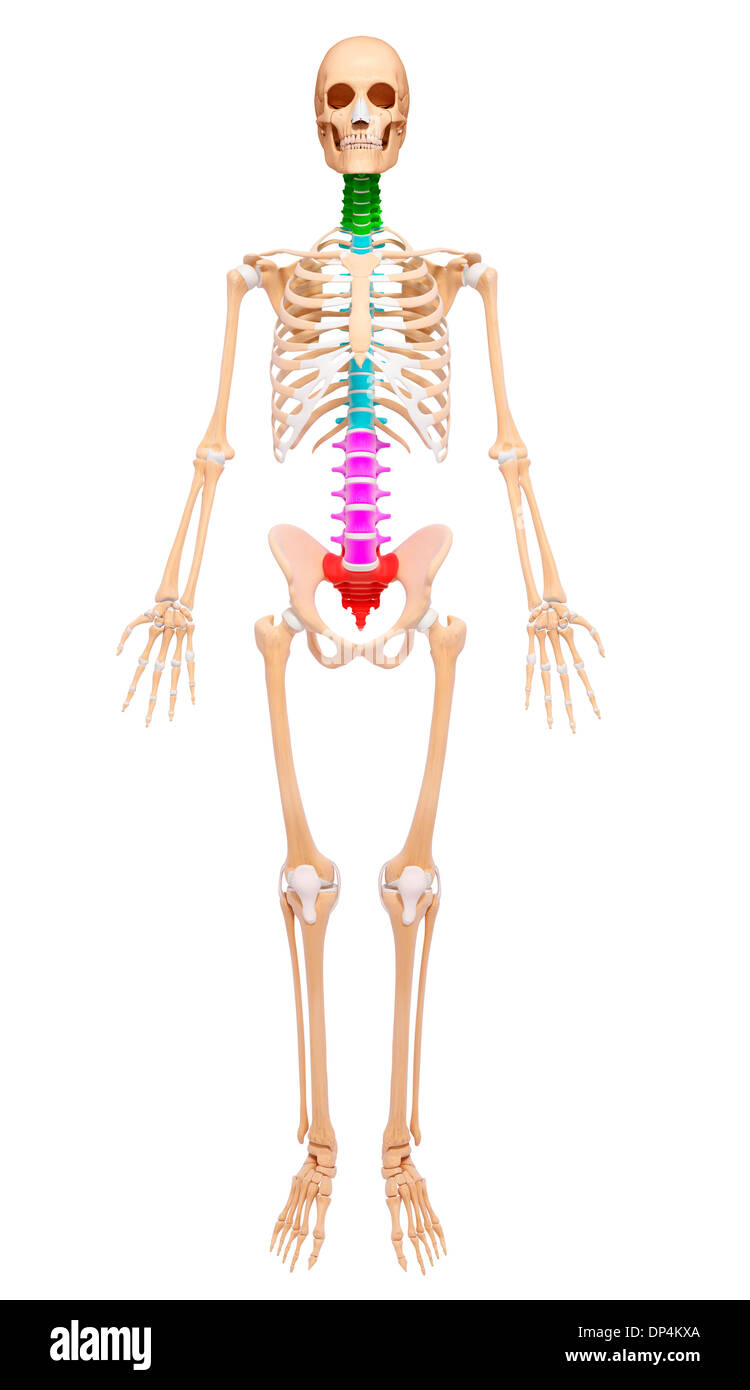

Human Skeleton, artwork Banque D'Imageshttps://www.alamyimages.fr/image-license-details/?v=1https://www.alamyimages.fr/human-skeleton-artwork-image65256978.html

Human Skeleton, artwork Banque D'Imageshttps://www.alamyimages.fr/image-license-details/?v=1https://www.alamyimages.fr/human-skeleton-artwork-image65256978.htmlRFDP4KXA–Human Skeleton, artwork